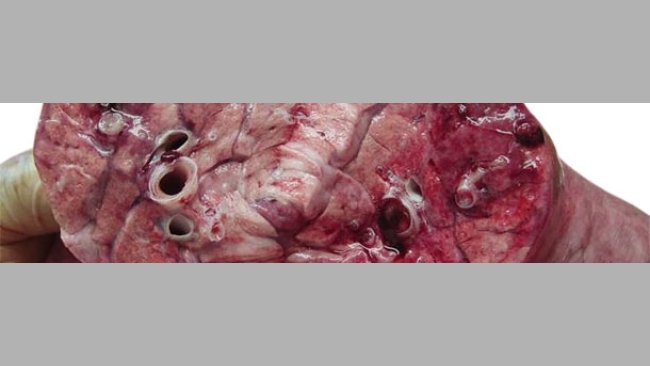

PED (Porcine Epidemic Diarrhoea) on the rampage